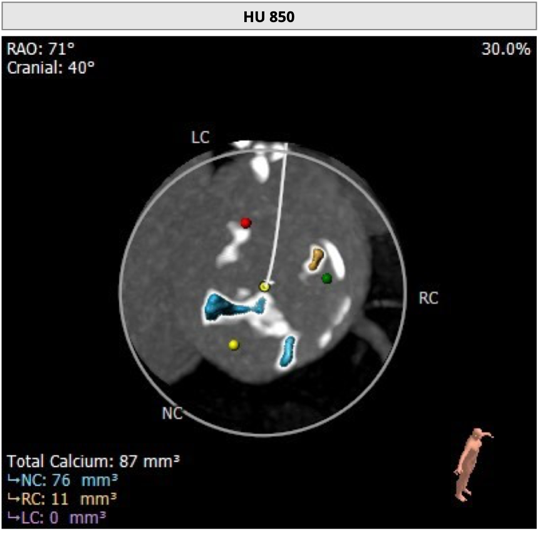

主动脉根部评估

CT 数据显示该患者为三叶式主动脉瓣

主动脉瓣瓣环周长75.6mm,周长径24.1mm;

LVOT 周长 74.1mm,周长径23.6mm;

SOV:28.5mm*31.6mm*29.4mm;

STJ 周长 93.9mm;

HU850:87mm³;

瓣环水平夹角52度。